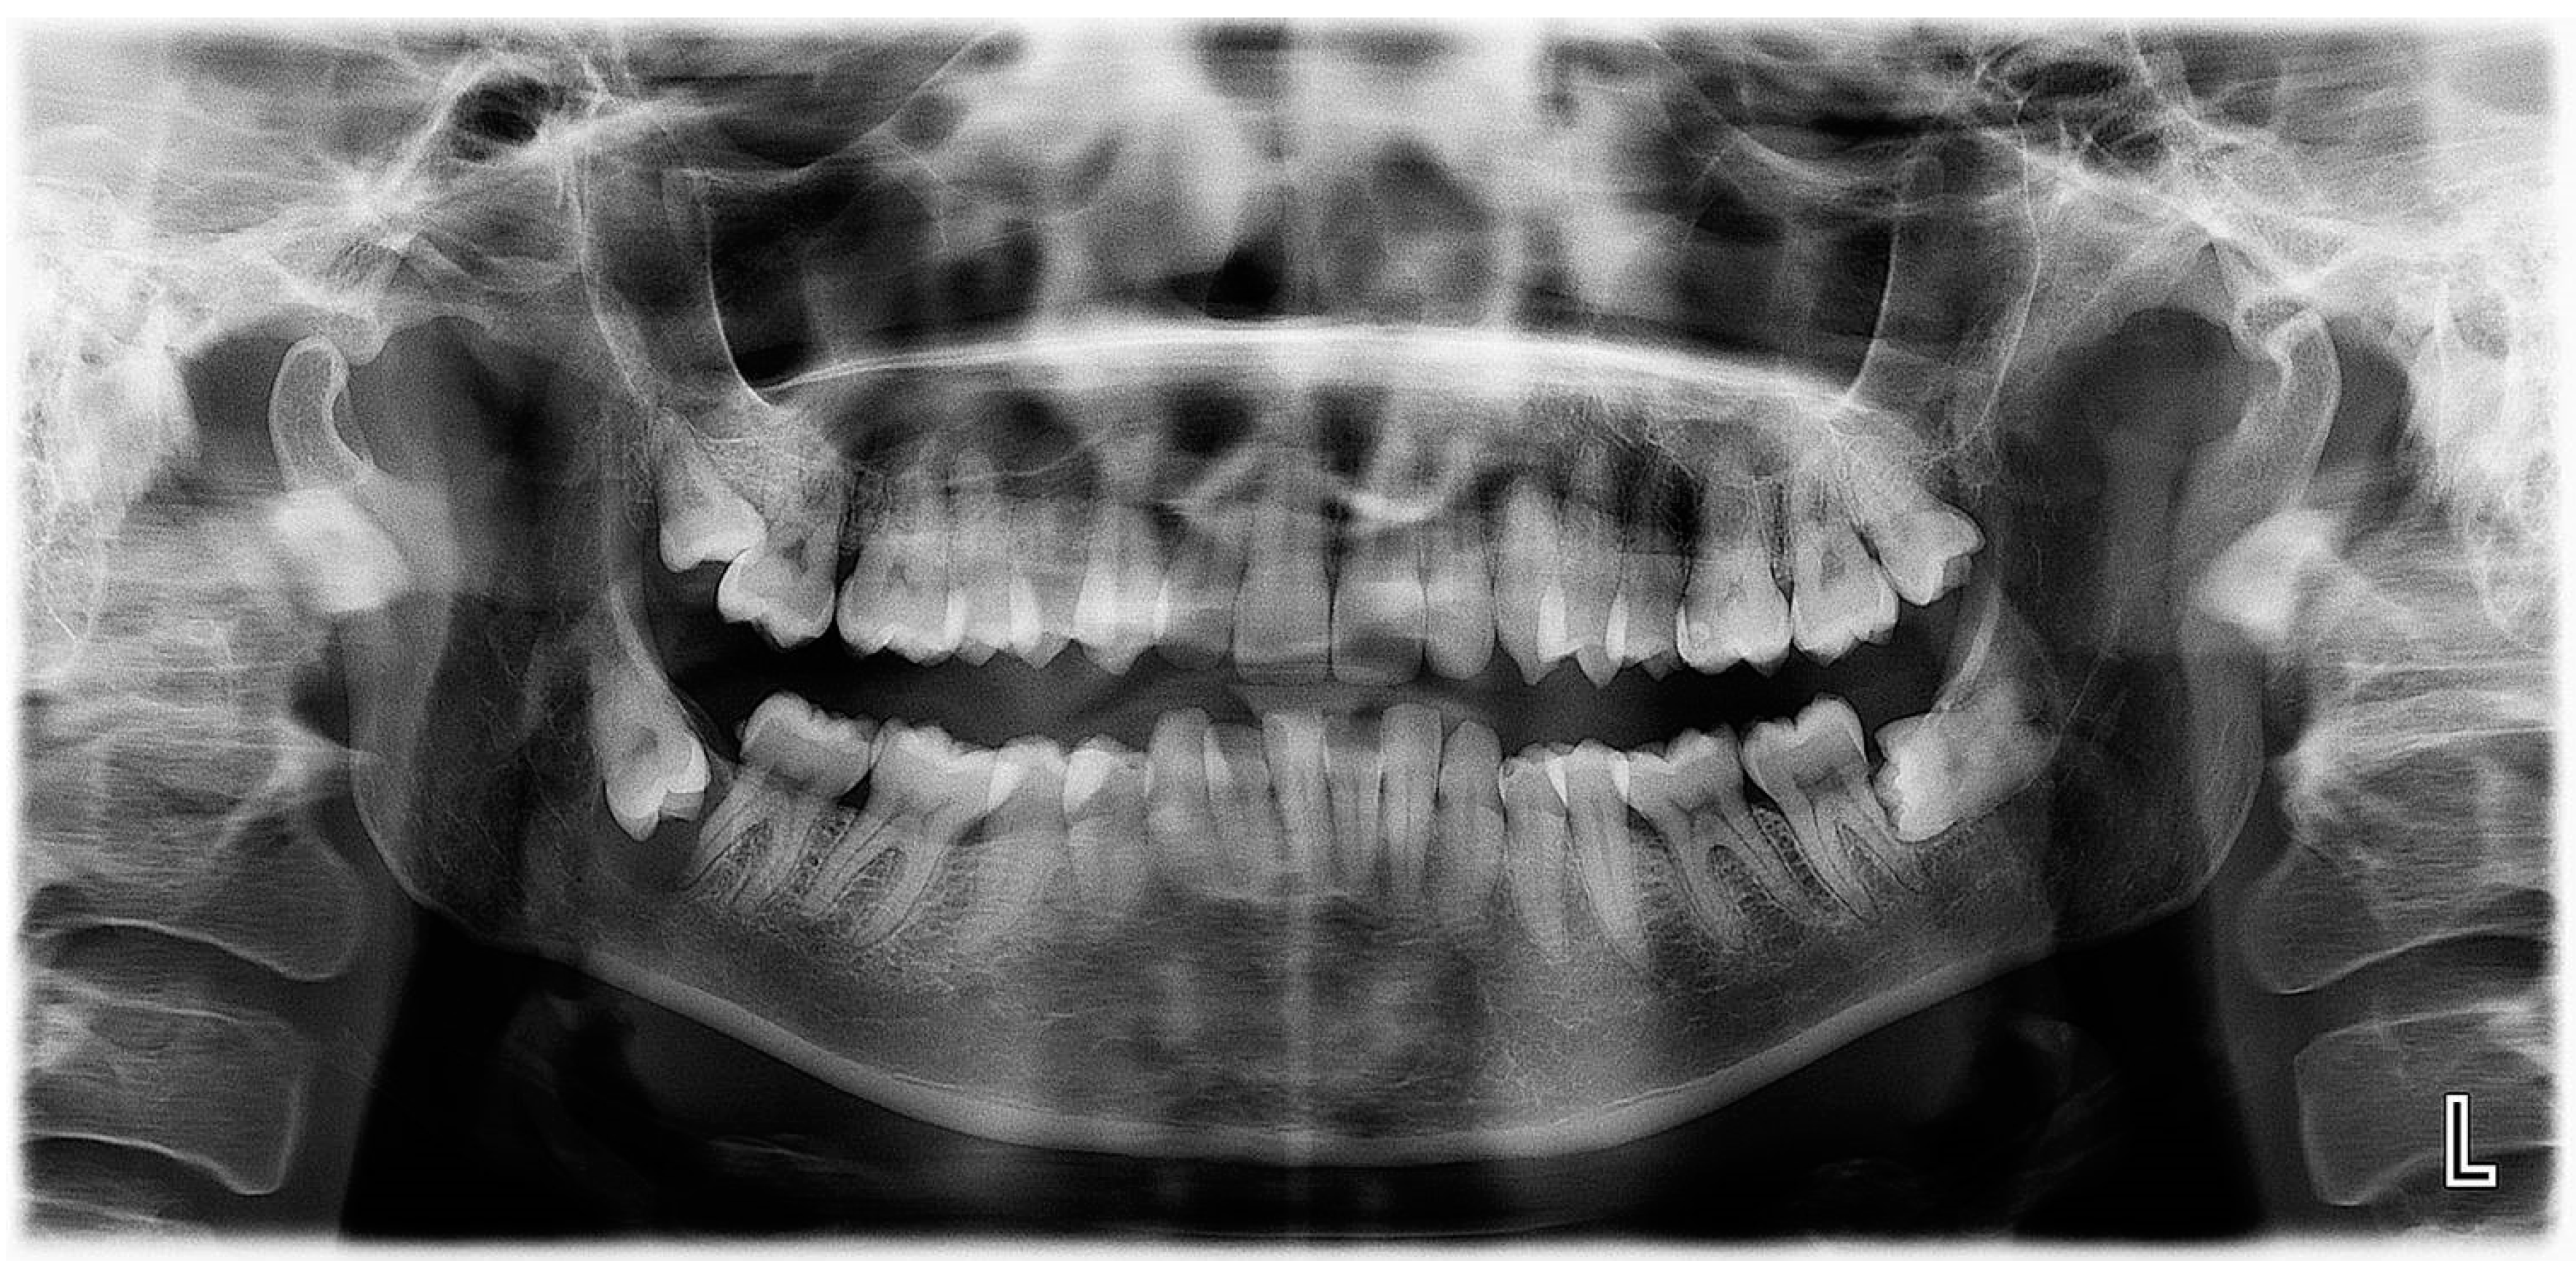

Panoramic radiography revealed the presence of a pericoronal radiolucent lesion around the crown of an impacted tooth #38 (horizontally positioned with mesial orientation) (Figure 1). The lesion measuring 27 × 22 mm was well defined and unilocular, surrounded by a thin sclerotic bone. It overlapped with the distal root of tooth #37, causing adjacent bone resorption but with no signs of root resorption. The cyst seemed to interfere with the inferior alveolar canal (IAC), which appeared displaced caudally by the lesion. A presumptive diagnosis of CD was made.

Figure 1.

Panoramic X-ray of case #1.